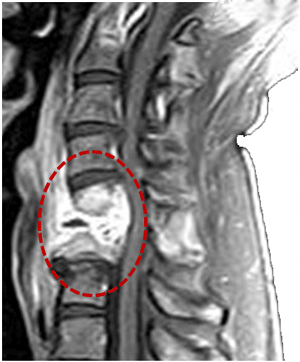

Tumor medular

Los tumores medulares se clasifican según su localización:

Tumor intramedular: son grupos de células que proceden del tejido nervioso, como los ependimomas o los astrocitomas. Suelen crecer de tal manera que deforman la médula espinal provocando daños neurológicos (déficits motores y/o sensitivos). En ocasiones forman quistes internos.

Tumor extramedular: son el resultado de una proliferación de las células que sostienen y mantienen las células nerviosas de la médula. Su crecimiento es externo a ella, pero provocan daño neuronal por compresión.